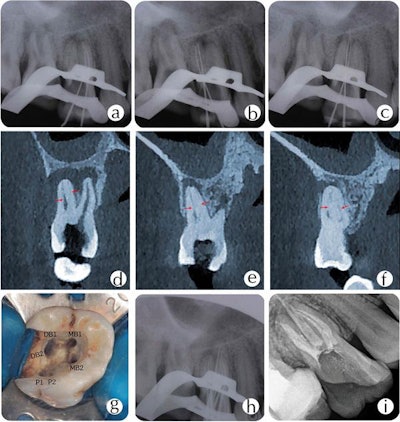

On radiographs, clinicians could see the pulp chamber was extended, the pulp floors showed apical displacement, the roots were short, and both teeth showed periapical translucency. The teeth were diagnosed as showing symptomatic apical periodontitis and mesotaurodonts. Mesotaurodontism is a classification of taurodontism in which the teeth are notably larger in size and have shortened roots and an enlarged pulp chamber.

Root canal therapy was recommended. Using a dental operating microscope, the dentist removed residual decay and prepared the access opening. Three orifice openings were identified in the pulp chamber. A closer look revealed complex patterns in both molars. An extra root canal orifice was concealed approximately 2 mm to 3 mm under the prepared canal orifice of the mesiobuccal and palatal canals in tooth #17.

CBCT scans gave a better view of the teeth and verified the findings. Clinicians prepared six canals in tooth #16 with two in the mesiobuccal root, two in the distobuccal root, and two in the palatal root. They also prepared seven canals in tooth #17: three in the mesiobuccal root, two in the distobuccal root, and two in the palatal root, the authors noted.

During root canal preparation, they could see that two of the canals in the mesiobuccal root of tooth #17 were joined together. The canals in the palatal roots were separated in the middle of the palatal root and met together in the third apical. X-rays and an electronic apex locator were used to determine the roots' working lengths. The preparation was completed, and the access cavity was sealed with temporary filling.